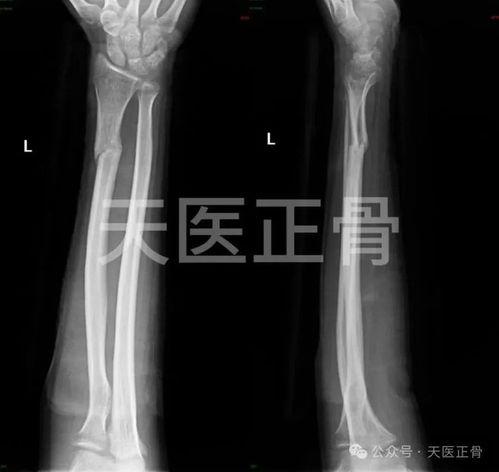

2. 胫腓骨骨折:胫腓骨骨折多发生在踝关节扭伤或跌倒时。